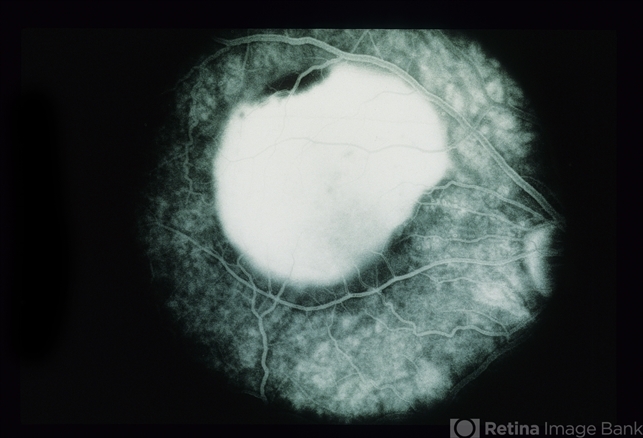

- Large Pigment Epithelial Detachment

- A 41 year old white woman presented with decreasing vision in her right eye over a four month period. Her visual acuity was 20/400 right eye, and 20/20 left eye. Ophthalmoscopy showed a large pigment epithelial detachment with overlying subretinal fluid in the right eye.